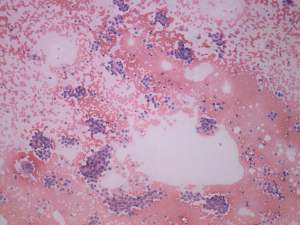

Histopathology. Papillary cancer in the left lobe with metastasis to the lymph nodes, and hyperplastic nodules in the right lobe.